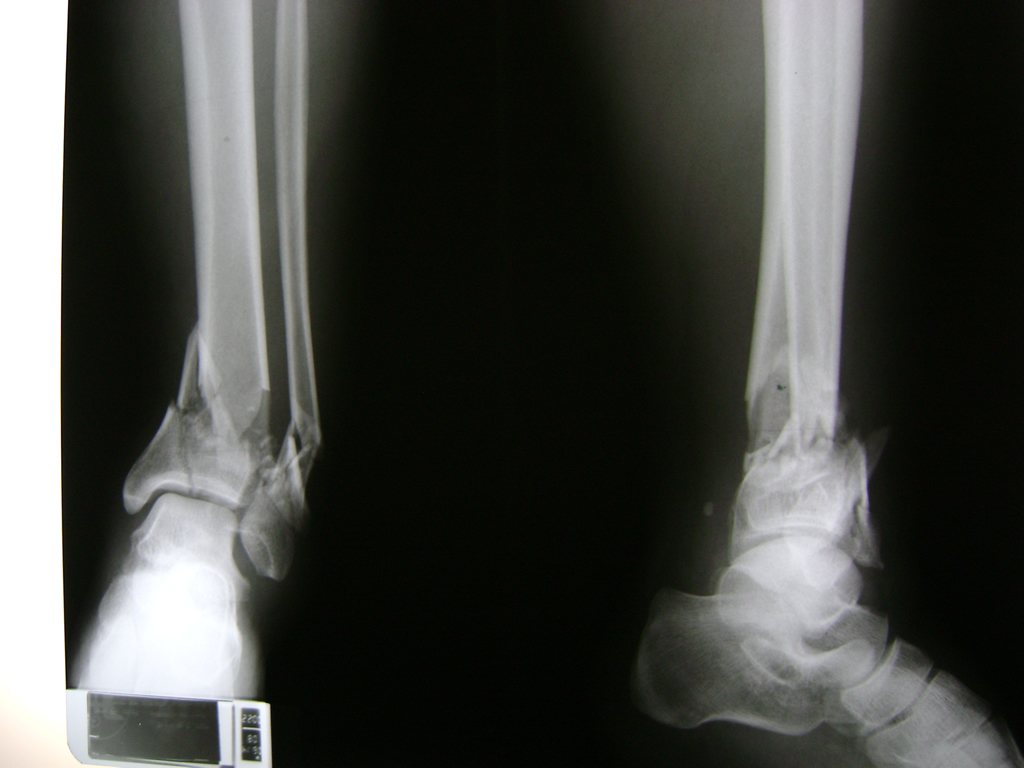

Una fractura de tobillo es la rotura de uno o más de los huesos del tobillo. Estas fracturas pueden ser:

Algunas fracturas de tobillo pueden requerir cirugía si:

- Los extremos de los huesos están desalineados entre sí (desplazados).

- La fractura se extiende hasta la articulación del tobillo (fractura intra-articular).

- Los tendones o ligamentos (tejidos que sujetan los músculos y los huesos entre sí) están rotos.